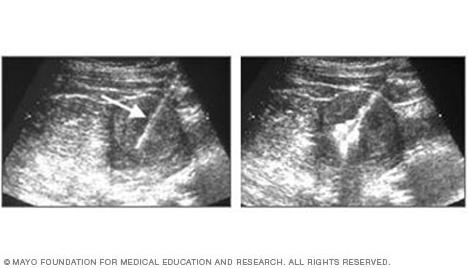

Ultrasound image showing a needle entering a tumor

Ultrasound of needle-guided procedure

These images show how ultrasound can help guide a needle into a tumor (left), where material is injected (right) to destroy tumor cells.